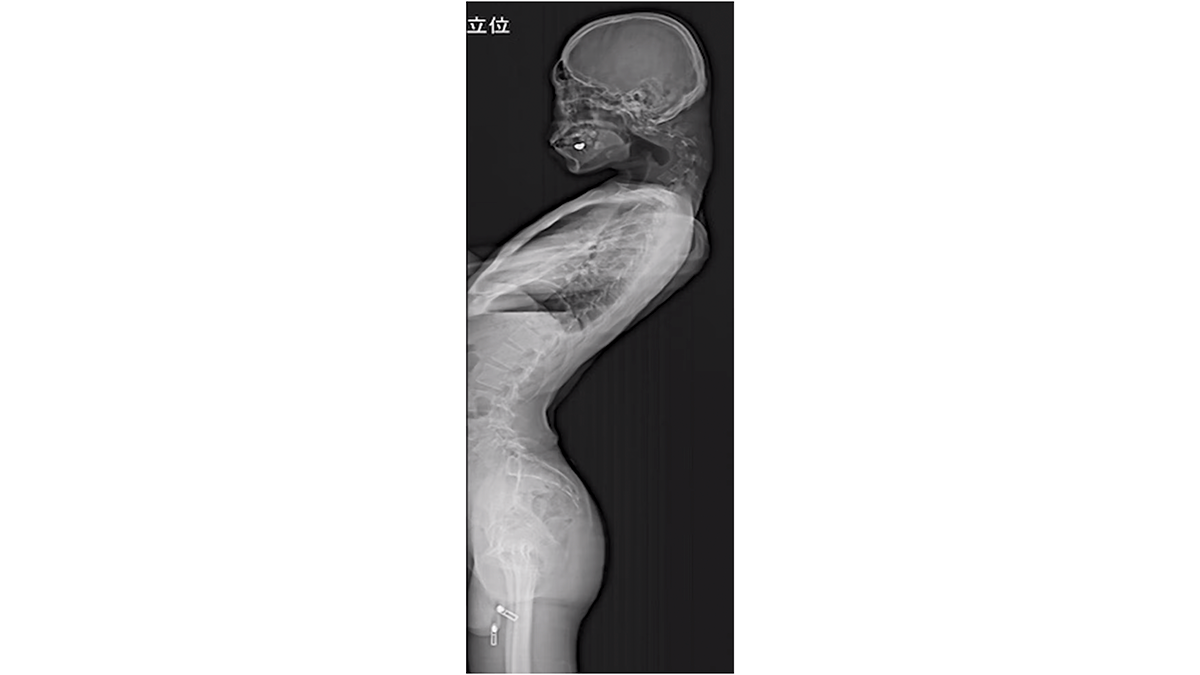

Nach oben

Ein 25-jähriger Gamer aus Japan, der über längere Zeit mit gebeugtem Kopf auf sein Handy schaute, verlor die Fähigkeit, den Kopf zu heben. Der Mann entwickelte eine große Beule im Nacken, schließlich ließ seine Nackenmuskulatur nach. Die Ärzte diagnostizierten das sogenannte Dropped-Head-Syndrom.

Gleichzeitig entwickelten sich Taubheitsgefühle in beiden Armen und Schwäche in der linken Hand. Es bildete sich zudem eine Beule an seinem Nacken. Als er erstmals das Unispital in Fukuoka aufsuchte, konnte er sein Kinn kaum von der Brust heben.

Medizinische Untersuchungen zeigten verzerrte und verschobene Halswirbel sowie Narbengewebe an seiner oberen Wirbelsäule, das durch anhaltende Überdehnung entstanden war.

Die Ärzte entschieden sich, den Patienten zu operieren. In mehreren Eingriffen wurden Teile der beschädigten Wirbel und des Narbengewebes entfernt und der Nacken anschließend durch das Einsetzen von Schrauben und Metallstäben stabilisiert, um seine Haltung zu korrigieren.